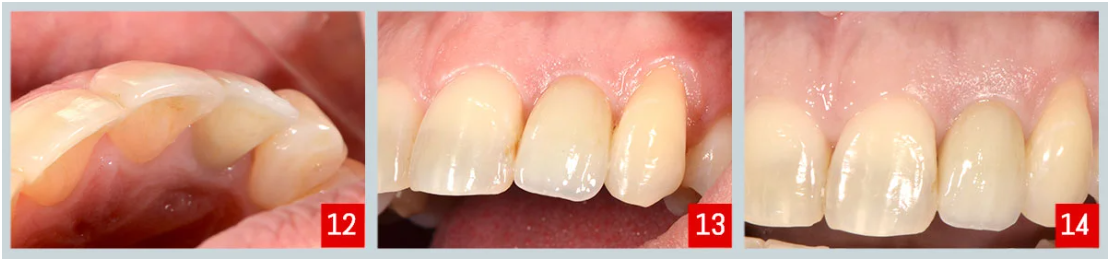

Resultado final : (imágenes 12, 13 y 14)

Se observó tejido blando sano y papilas conservadas tanto en la zona mesial como en la distal alrededor de la restauración final.